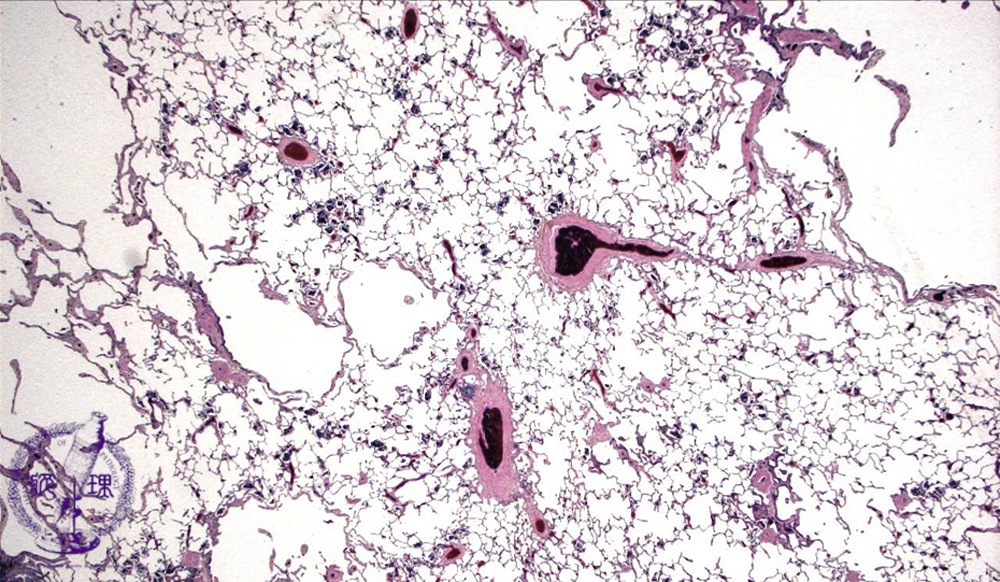

Microscopic view (HE stain, low power view): Scattered irregularly dilated air spaces are seen due to peripheral respiratory bronchiole destruction.